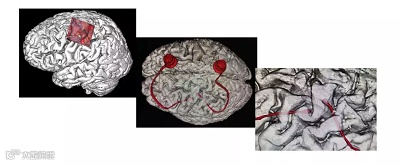

术后复查确认电极植入位置无误。图片来源:浙大二院

0.1毫米的手术机器人面世!为了保证损伤其他神经。研究人员采用步进为0.1毫米的手术机器人,将2个微小感应的智能电极阵送入大脑最深处的既定神经元细胞位置,注意!要精确到细胞位置!

“在4毫米×4毫米大小的微电极阵列上浙大的医生放置了有100个电极针脚,每一个针脚都可能检测到1个甚至多个神经元细胞放电。